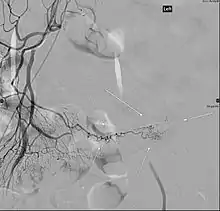

Patients with these misplaced gastric cells may experience peptic ulcers as a consequence. Therefore, other tests such as colonoscopy and screenings for bleeding disorders should be performed, and angiography can assist in determining the location and severity of bleeding. Colonoscopy might be helpful to rule out other sources of bleeding but it is not used as an identification tool.

Angiography might identify brisk bleeding in patients with Meckel's diverticulum.[21]